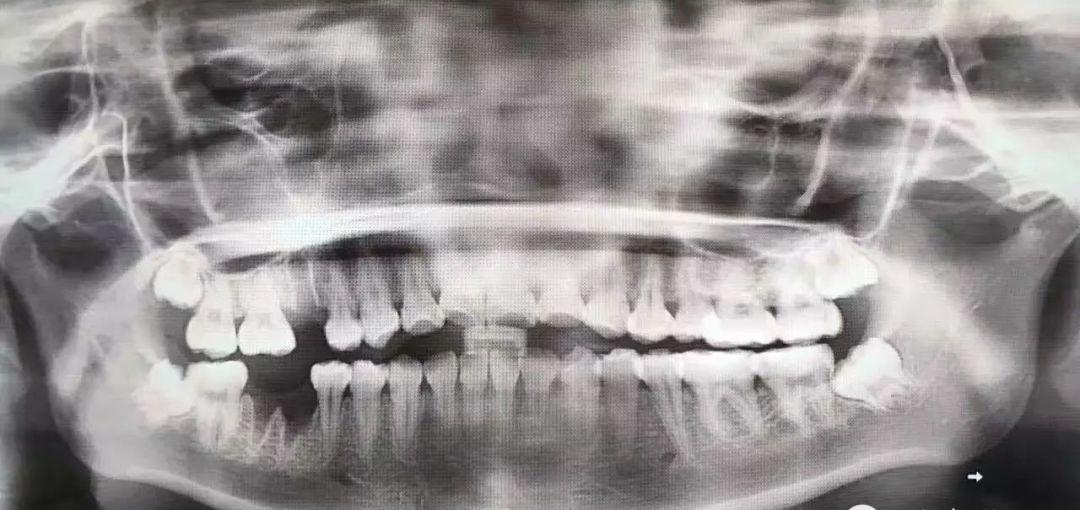

傳說(shuō)中收費(fèi)14000的牙長(zhǎng)這樣子——

而同行則認(rèn)為,這個(gè)收費(fèi)有點(diǎn)太那么不厚道

真真假假,假假真真。智齒是否值上萬(wàn)元的價(jià)格,對(duì)這樣的事情,我們無(wú)法做出準(zhǔn)確的評(píng)估,還有待專業(yè)人士的評(píng)價(jià)。但毋庸置疑的一點(diǎn)是,拔除智齒,尤其是埋得深度較高,傾斜度不同,或者是下頜貼近神經(jīng)管的智齒,收費(fèi)程度肯定比普通拔牙要貴,這確實(shí)是真的